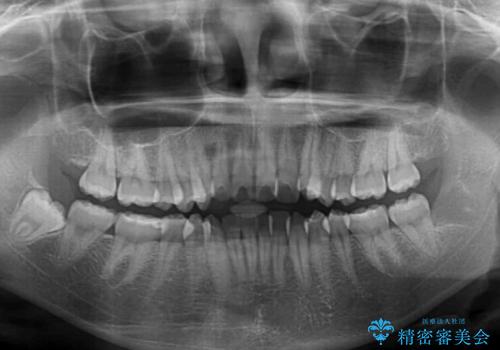

インビザラインでの治療を希望されていましたが、前歯のクロスバイトや下顎小臼歯の捻転が認められたため、インビザライン単独で治療を行うよりも、ワイヤー装置を併用した方が、治療期間の短縮やトラブル回避できると判断し、ワイヤー装置を併用することとしました。

前歯のクロスバイトは、インビザラインでの改善中に前歯に過剰な力がかかり、歯髄壊死や歯肉退縮を引き起こすことがあります。また下顎小臼歯は寸胴型のため、捻転を排除することが難しいことが知られています。

それをワイヤー装置にて速やかに改善することで、トータルでの治療期間を短くすることができます。